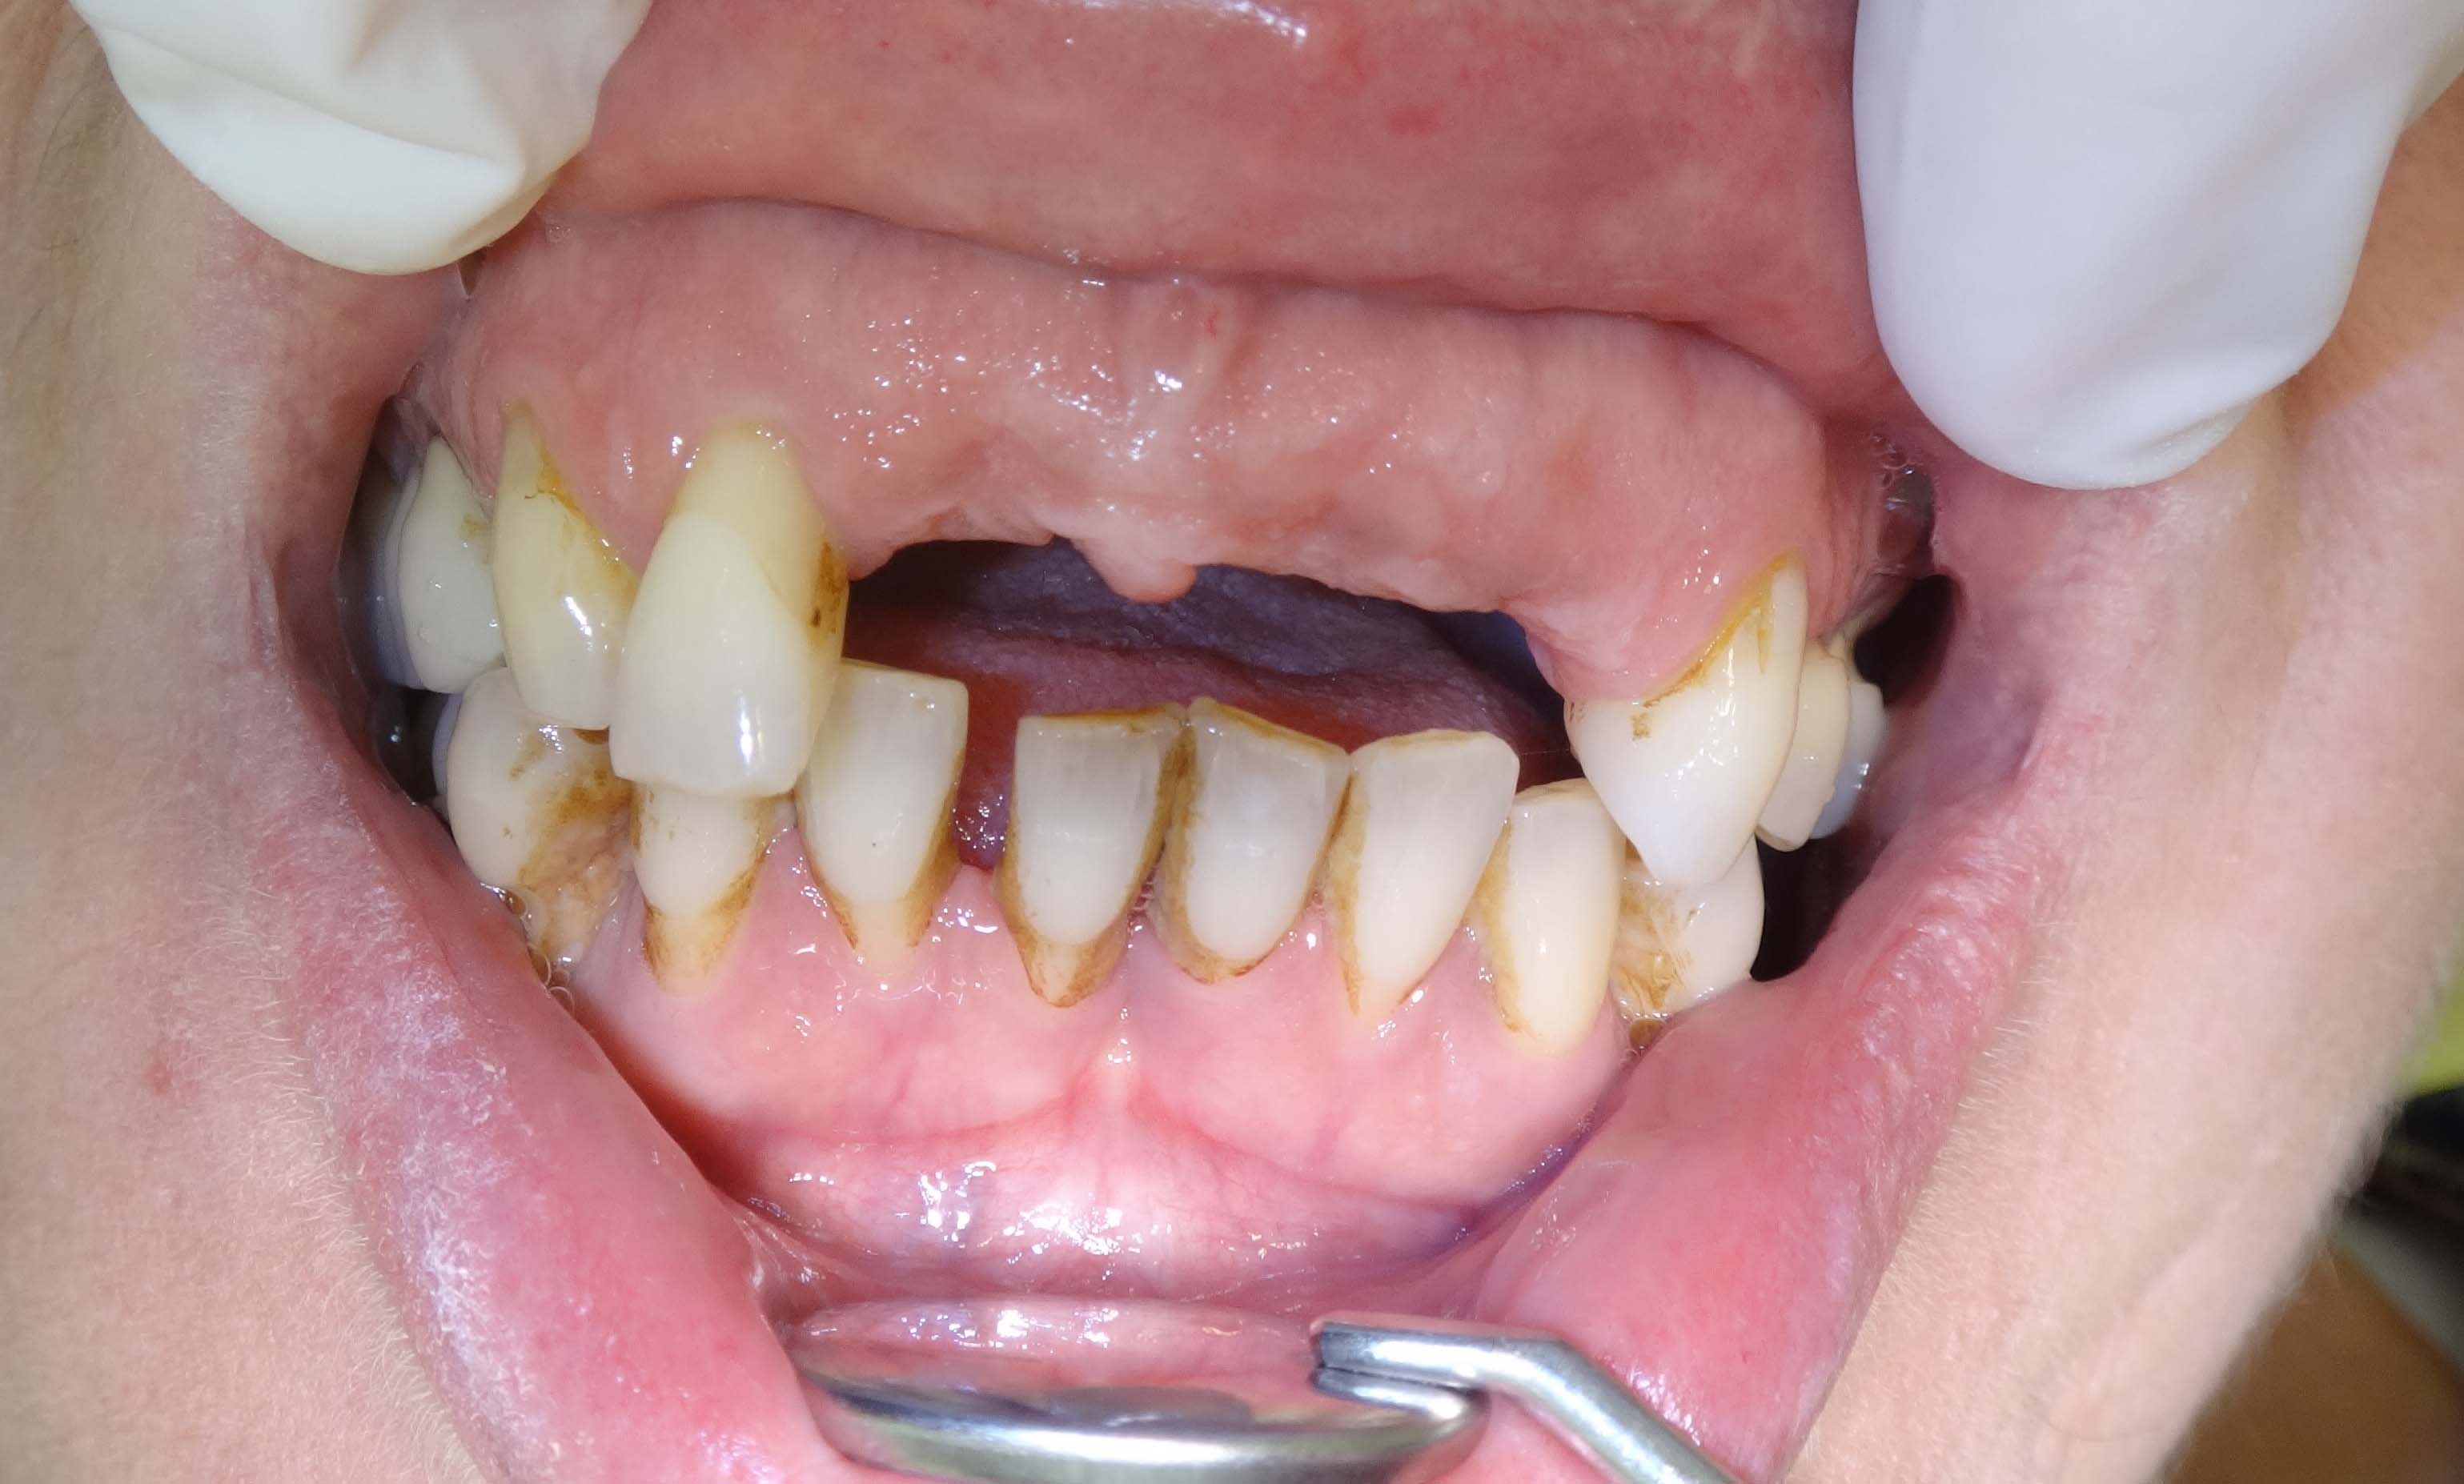

Le temps qu'elle se décide à faire quelque chose on se retrouve en 2013 avec cette photo du secteur antérieur.

L'occlusion est en classe II +++.